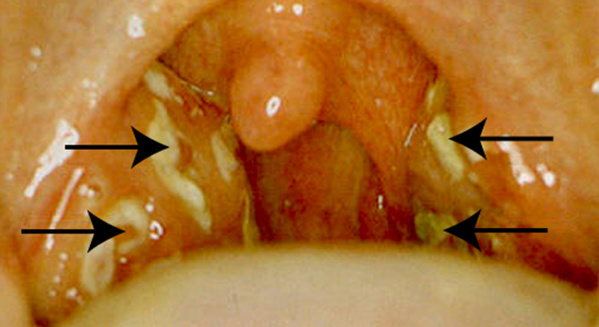

Les amygdales sont très rouges, enflées et sont recouvertes de rayures ou points jaunes clair